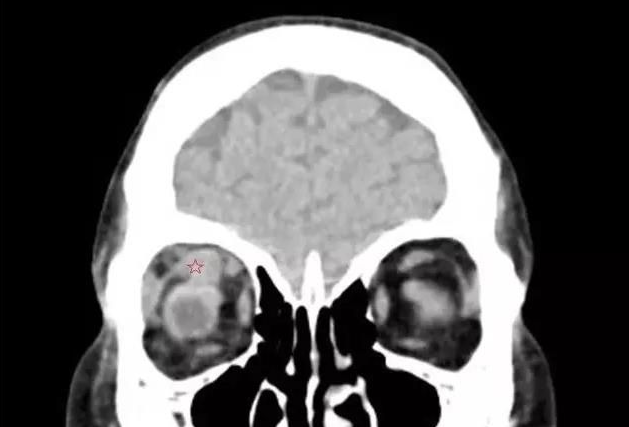

来自泉州南安的刘先生发现自己的眼睛莫名的越来越突,还容易流眼泪,转动不灵活,看东西模糊,一个东西变成两个,看马路上的车一辆变成两辆,上下楼梯也踩不准,并且脾气变得暴躁。在当地医生的建议下,今年4月,刘先生又来到了厦门眼科中心斜视与小儿眼科检查,谢仁艺副主任医师在询问了解了刘先生的病情后,并结合各项检查报告判定刘先生是患了甲状腺相关眼病。

谢仁艺副主任医师介绍,刘先生眼睛病变是因甲亢引起,导致双眼眼外肌发炎、肿胀、变性、纤维化, 终失去弹性,这也是他眼球转动不灵活引起斜视、复视的主要原因。